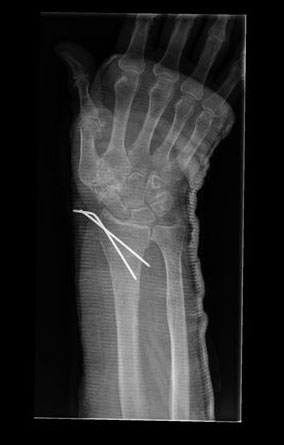

Tratamiento de fractura de radio con agujas.

|

Tratamiento con agujas de fractura de radio.